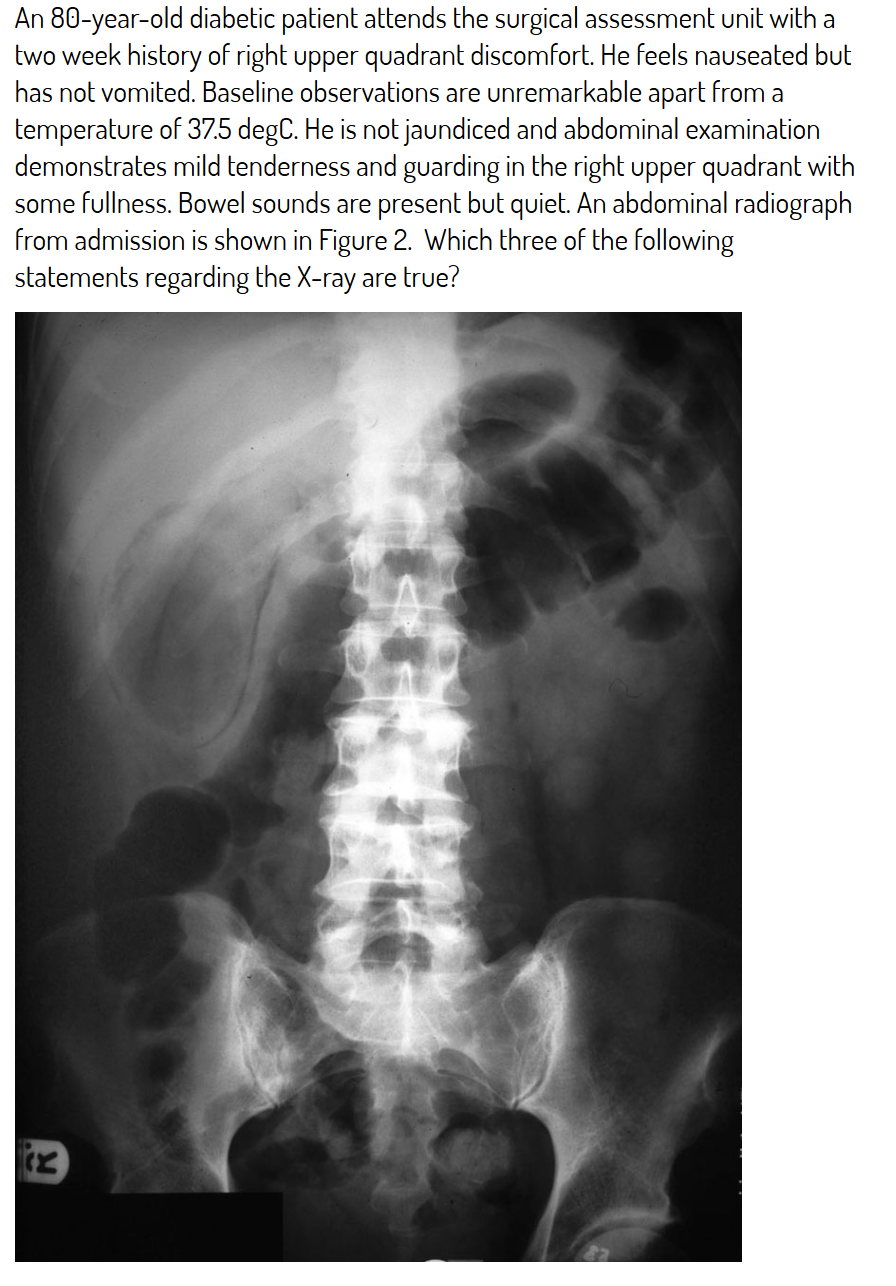

The gallbladder is distended and thick-walled and curvilinear lucency in keeping with gas is seen in the gallbladder wall.

Which of these is true about air in the gallbladder wall?

More common in diabetics

CT is the ideal modality for delineation and is superior to US

Symptoms and signs are initially minor but mortality is high - Initial symptoms/signs are often minor but mortality due to sepsis is high. Oedema changes obstruct the cystic duct with distension/ischaemia of the gallbladder and sepsis supervenes

It is known as emphysematous cholecystitis

Air in the wall arises as a combination of gallbladder ischaemia and infection with gas-forming organisms

Treatment is surgical.